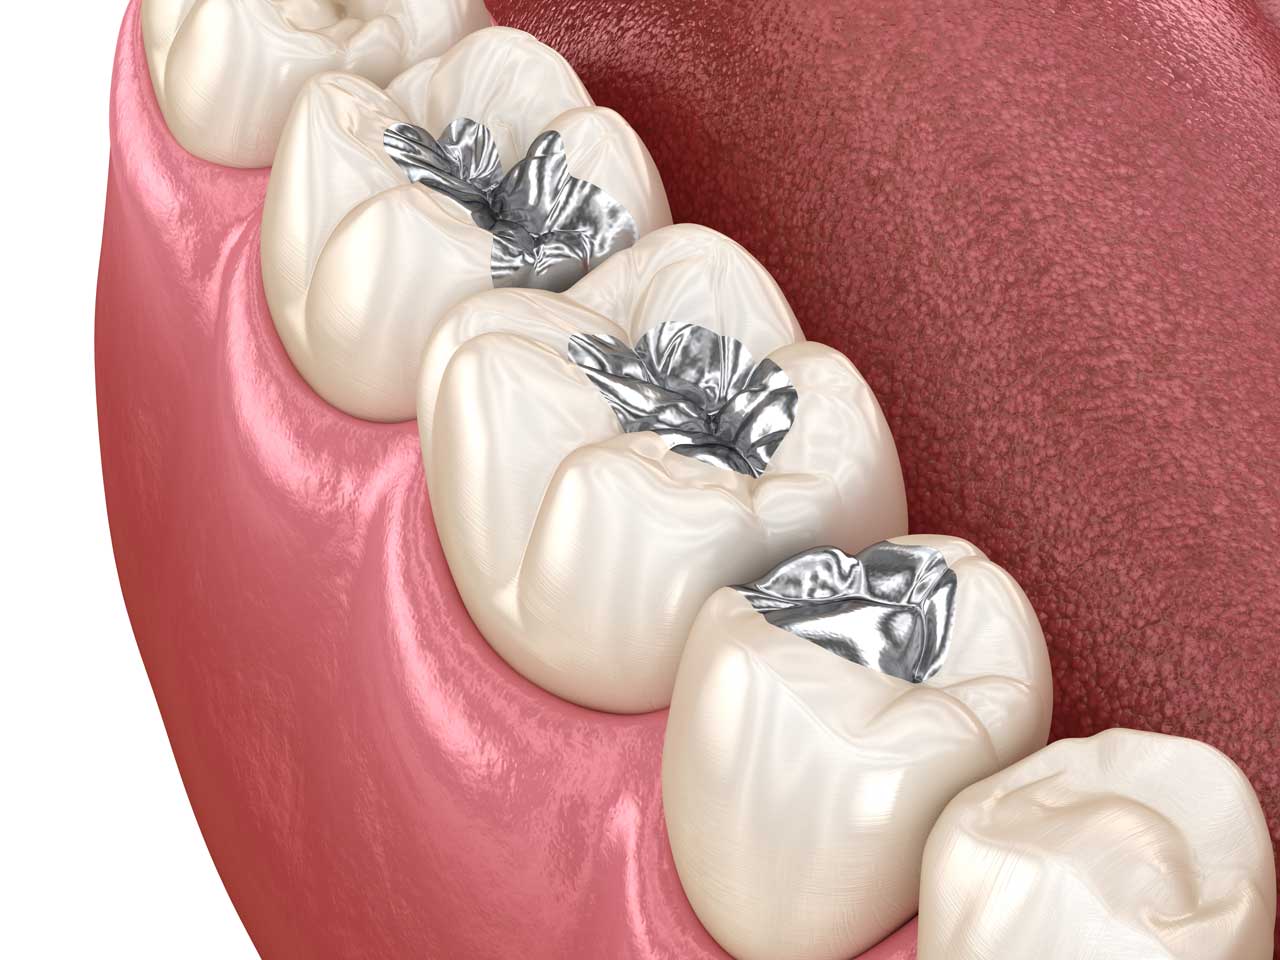

Tooth filling restores cavities and damaged teeth, preventing further decay and improving function, while maintaining a natural, healthy smile.